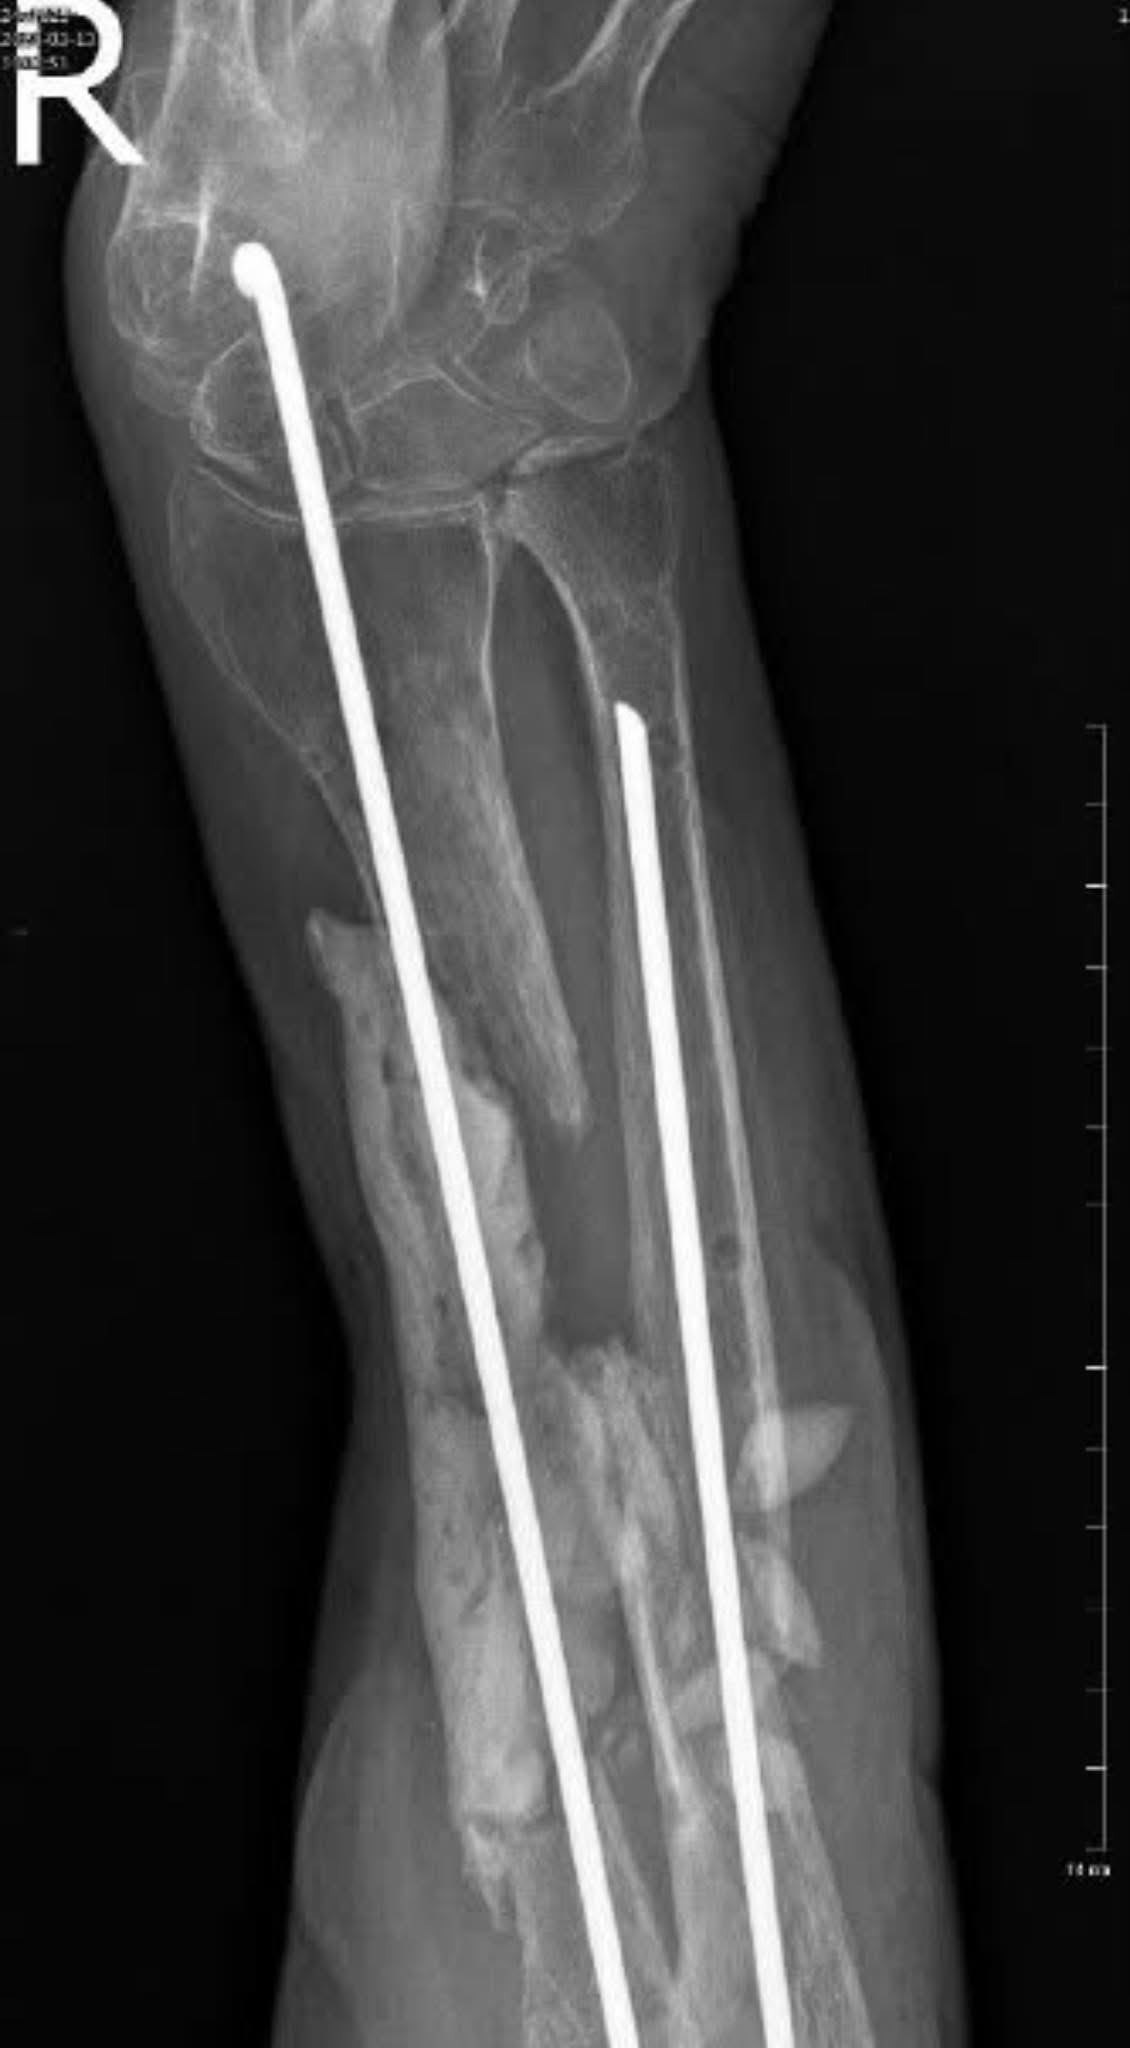

• Відкрита репозиція,

• Відновлення осі та довжини передпліччя,

• Мостовидний остеосинтез променевої кістки блокуючою реконструктивною пластиною,

• Видалення спейсера і заміщення дефекту аутокісткою з біосклом Bonalive,

• Остеосинтез ліктьової кістки блокуючою пластиною.

Операція тривала близько 7 годин.